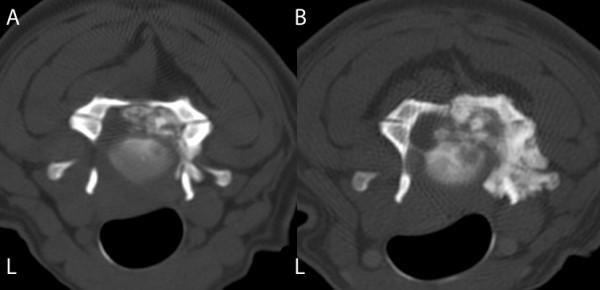

A ten-year-old male standard dachshund was presented with a history of neck pain and progressive gait disturbances. Following a neurological examination and diagnostic imaging, including CT, a neoplastic lesion involving the third and fourth cervical vertebrae was suspected. The lesion included an extradural mass on the right side of the spinal canal causing a local compression of the cervical cord. Surgery, using a modified dorsal laminectomy procedure, was performed in order to decompress the cervical spinal cord. Histopathological examination of the extradural mass indicated that the tumour was a chondroid chordoma. Following discharge, the quality of life for the dog was very good for a sustained period, but clinical signs recurred at 22 months. The dog was euthanased 25 months post-surgery. On post-mortem examination, a regrowth of neoplastic tissue was found to have infiltrated the bone and spinal cord at C3-C4. This is the first report to show that palliative surgery can offer successful long-lasting treatment of chondroid chordoma of the cervical spine in the dog.

一只十岁大的雄性标准贵宾犬,出现颈部疼痛和进行性步态障碍的病史。经过神经学检查和包括 CT 在内的诊断影像学检查后,怀疑第三和第四颈椎有肿瘤病变。病变包括椎管右侧的硬膜外肿块,导致颈脊髓局部受压。为了对颈脊髓进行减压,采用改良的背侧椎板切除术进行了手术。硬膜外肿块的组织病理学检查表明肿瘤为软骨脊索瘤。出院后,狗狗的生活质量在很长一段时间内都非常好,但在 22 个月时临床症状再次出现。手术后 25 个月,狗狗被实施了安乐死。尸检时发现,C3-C4 处的骨和脊髓有肿瘤组织再生并浸润。这是首例报道显示姑息性手术可以为犬颈椎软骨脊索瘤提供成功的长期治疗。